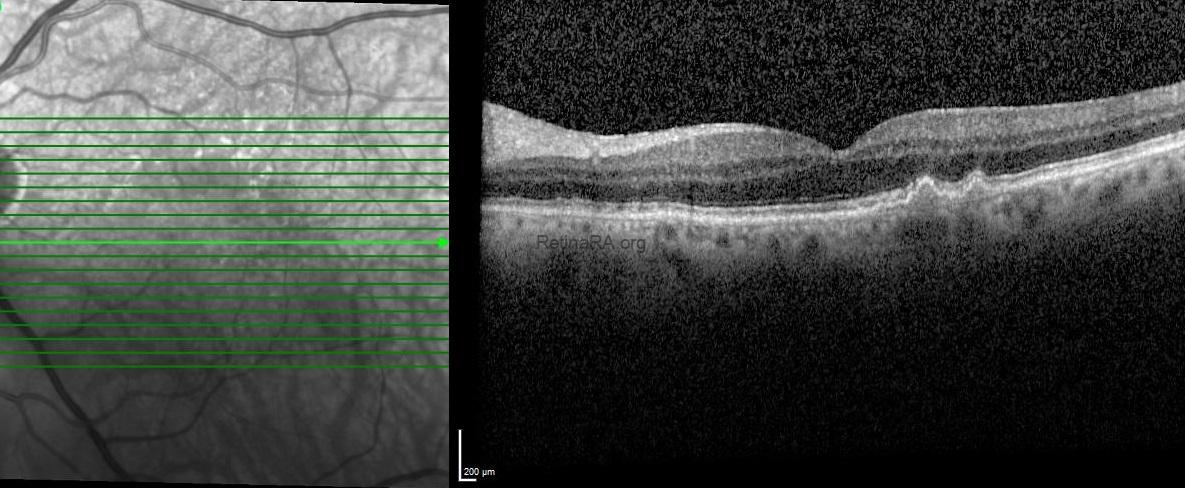

Optical coherence tomography (OCT) exhibited retinal thickening, intraretinal cystic spaces and serous retinal detachment in the right eye and subretinal drusenoid deposits and drusenoid pigment epithelium detachment with normal foveal contour in the left eye.

3 times per day was recommended. One-month after the topical treatment, the BCVA of the right eye improved to 20/25 and OCT showed the complete resolution of subretinal and intraretinal fluid.